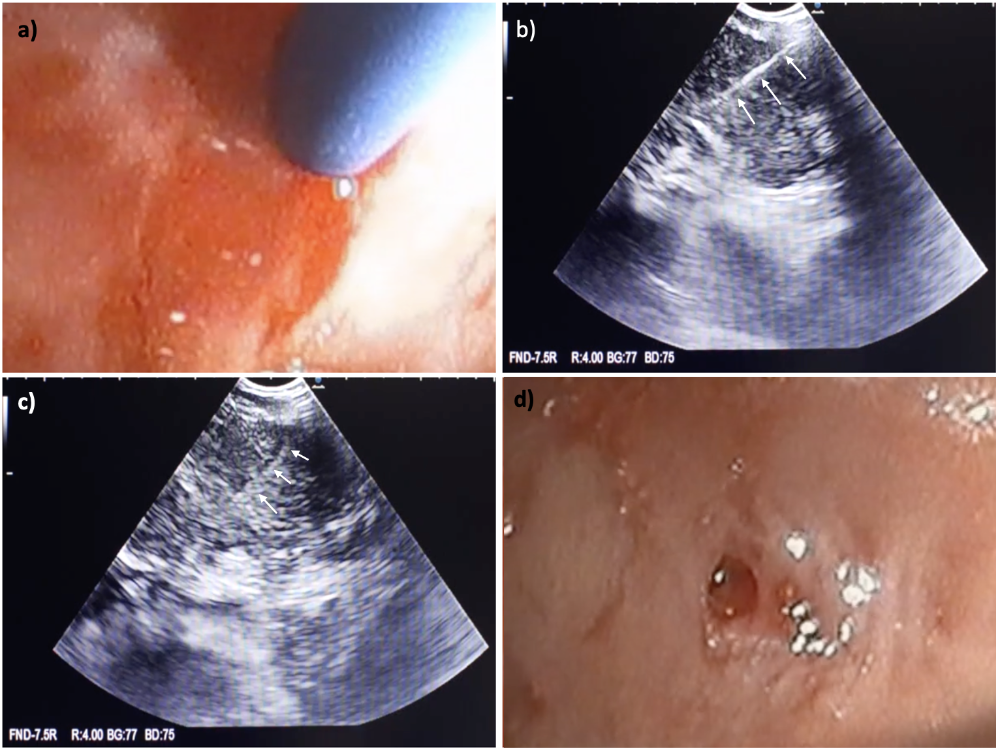

Figura 2. (a) Realización de EBUS-TBNA en estación ganglionar 7; se observa la vaina de la aguja TBNA. (b) Imagen ecográfica del ganglio linfático con la aguja de 22G en su interior (flechas blancas). (c) Trazado ecográfico del trayecto dejado por la aguja tras tres punciones (flechas blancas). (d) Sitio de punción observado por EBUS tras retirada de la aguja (flechas blancas).

Figura 3. (a) Punta de la criosonda aproximándose al trayecto de punción. (b) Imagen EBUSDoppler mostrando la punta de la criosonda de 1,1 mm dentro del ganglio (flecha blanca). (c) Muestra de criobiopsia adherida a la punta de la criosonda. (d) Ausencia de sangrado posterior a la criobiopsia.